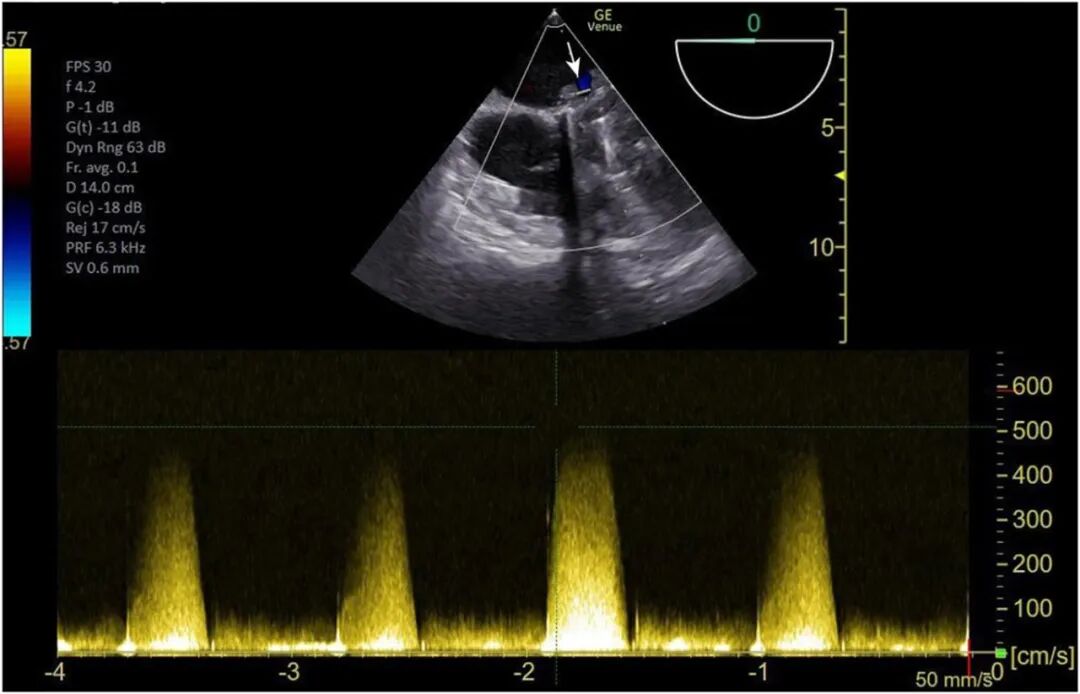

图2 连续波多普勒显示二尖瓣舒张期前向血流峰值流速为5m/s(箭头)。